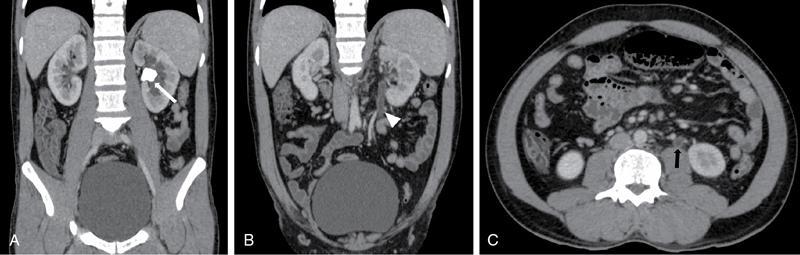

Fig. 10.14.2 Ureteritis: Coronal post-contrast (A and B) and axial post- contrast (C) images in a 30-year-old patient with right flank pain, burning micturition and pus cells on routine Urine examination: Left pelvi-ureteric junction calculus (white arrow in A) is seen causing mild hydronephrosis. There was enhancing thickening of proximal ureteric wall on left side (white arrowhead in B and black arrow in C) with prominence of ureteric lumen without any distal filling defect.